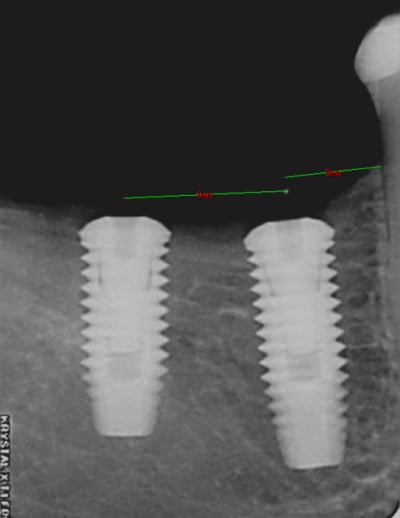

Je voulais vous faire découvrir un petit outil que j'ai inventé et fait fabriqué pour m'aider dans le positionnement d'un ou plusieurs implants , au cours de la chirurgie.

C'est sur que c'est a des années lumières des guides ultra sophistiqués de chirurgie guidée, mais je peux vous assurer que je m'en sert tous les jours et pour un moindre cout.

en PJ vous trouverez une photo de la bête ainsi qu'un article explicatif.

je viens de faire ma première pose avec "the" outil (merci clio pour la livraison ultra-rapide:)

remplacement de 46 et 47

Petite bouche mais ouverture pas trop limitée. Pour 46, point de forage à 5 mm de la 45 (3 ème cran contre la 5 et forage au milieu de la gorge centrale) puis pour la 47 j'ai choisi de forer à 8 mm du point de 46 en raison de l'antagoniste (je vais faire une "petite" 47)

mes impressions: très très pratique (çà fait même un peu écarte-joue)